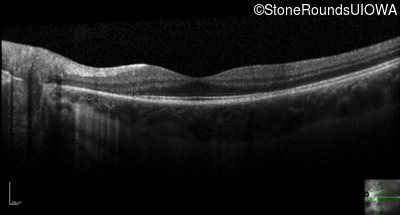

Optical Coherence Tomography - Right - 20/20

Exemplar / OCT Stack

Optical Coherence Tomography - Left - 20/20 -2